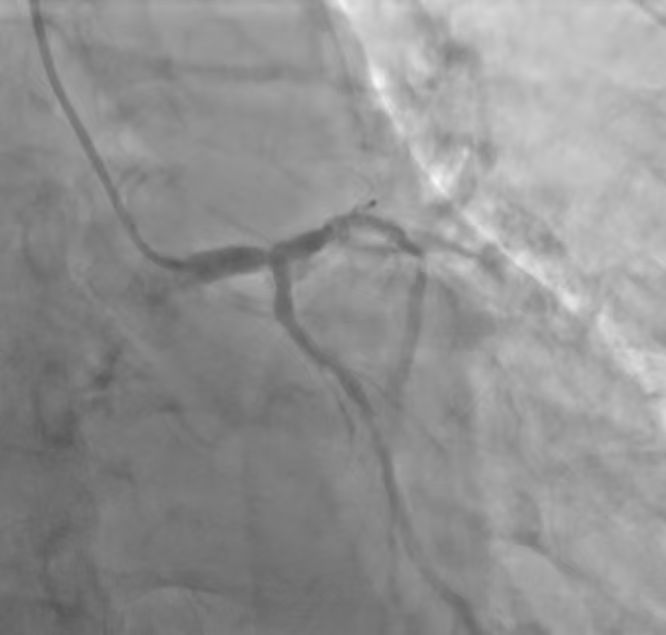

何爷爷早前就在当地医院被诊断出主动脉狭窄,但未予重视。近一年来,一次肺炎诱发了心力衰竭,导致何爷爷活动后胸闷、气促的症状加剧且频繁发作,日常生活受到严重影响。入院后,全面检查提示了患者的病情凶险程度。心脏彩超显示,主动脉瓣和二尖瓣这两个核心“阀门”出现严重病变,致使心脏功能急剧恶化;冠脉造影结果更为棘手,不仅存在两支血管病变伴钙化,最狭窄处甚至达到了75%。如此复杂危重的状况,使得手术成为唯一有效的治疗方案,但也意味着极高的风险,这对医疗团队的技术与协作提出了空前挑战。

患者术前冠脉造影提示双支血管病变合并钙化